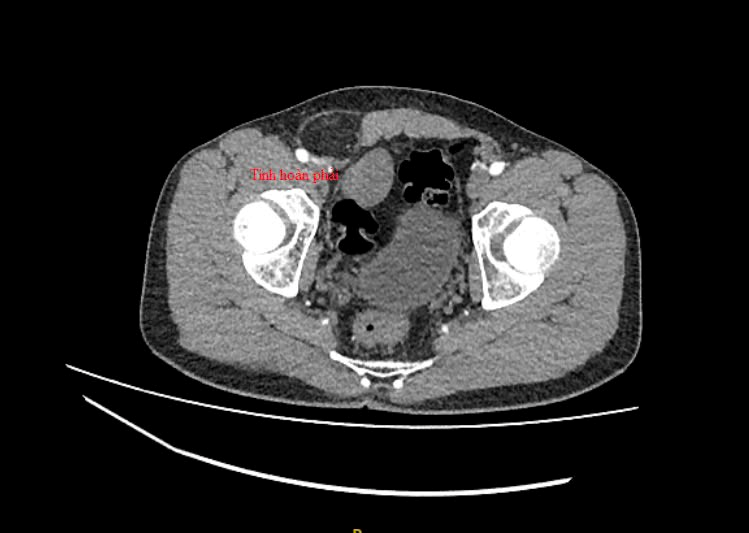

Qua kiểm tra hình ảnh, bác sĩ phát hiện khối thoát vị bẹn, đồng thời tìm thấy tinh hoàn bên phải trong ổ bụng nằm cạnh bàng quang của bệnh nhân. Sau hội chẩn, các bác sĩ đã quyết định thực hiện phẫu thuật cho người bệnh.

Trong quá trình phẫu thuật, ê kíp bác sĩ đã đưa các tạng thoát vị vào trong ổ bụng. Các bác sĩ đã thám sát và xác định tinh hoàn bên phải của bệnh nhân có kích thước tương đương tinh hoàn còn lại. Tinh hoàn bên phải nhanh chóng được giải phóng và đưa từ ổ bụng về vị trí sinh học ở vùng bìu cho bệnh nhân. Sau phẫu thuật, sức khỏe người bệnh nhanh chóng bình phục.